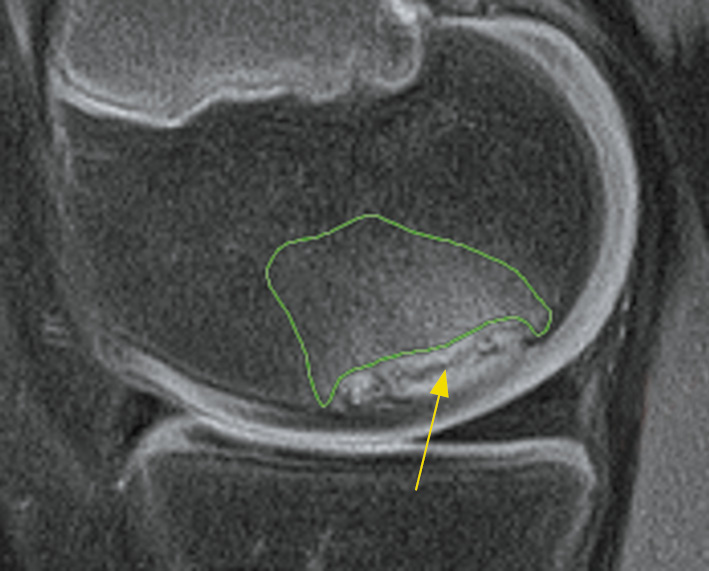

Figure 1 shows a knee joint MRI (sagittal proton density fat-saturated (PD-FS) image) of a child with an OD lesion. The continuous line indicates the segment of increased intensity in the bone’s maternal part, corresponding to the bone substance edema. The latter occupies approximately 25% of the condyle.

Fig. 1. Magnetic resonance imaging of the knee joint of a child with a focus of osteochondritis dissecans in PDFS mode in the sagittal projection. The continuous line marks the area of increased intensity in the maternal part of the bone, corresponding to the edema of the bone substance. The latter occupies approximately 25% of the condyle. The arrow indicates the hypointense band between the osteochondral fragment and the maternal bone. The latter occupies about 80% of the length of the entire lesion from front to back, with mosaic hyperintense areas corresponding to the bone tissue that still partially connects the fragment to the maternal bone.

The arrow in Figure 1 indicates a hypointense band between the osteochondral fragment and the maternal bone, with the latter occupying approximately 80% of the length of the entire lesion anteroposteriorly. The hyperintense areas have a mosaic arrangement that corresponds to the bone tissue that still partially connects the fragment to the maternal bone.